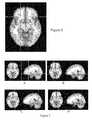

FIGS. 5-8 are brain images comprising a reliability map according to some embodiments.

As shown inFIG. 4, in this dataset, within a given voxel, there is a finite chance (peaking near 5%), that a given voxel will meet the selected statistical threshold among the analyses. The x-coordinate is represented as “percentage of total t-tests”, but in the case of an analysis with a different focus, it could represent a different statistical test. In the represented sample, the 100% hash mark is reached at 2,000 analyses. We can see that among analyses, a progressively smaller proportion of the sample meets threshold. A two-dimensional slice from a three-dimensional map, derived from a similar clinical population, is shown inFIG. 5. In this map, which can be termed a “reliability map” or “variability map” with respect to the selected threshold, it can be noted that certain voxels, and associated regions, supercede the selected threshold in a large proportion of analyses (denoted in this case by warm colors and reds), whereas other voxels, and associated regions supercede the selected threshold in only a limited number of analyses (denoted by cool colors or blue-green colors).

A map of potential use for prediction is therefore constructed. For example, using this map a series of anatomic regions may be selected including the voxels selected at a particular stringency, such as the largest 5 or 10 regions. As another example, a selection rule may be used, such as selecting the large 5 regions for example, and any contralateral region corresponding to the selected region when located in a mirrored location in the other hemisphere.FIG. 6 shows how this might be performed referring to a particular analysis. For example, the region encircled on the right is one of the larger regions of difference differing between the two populations among the repeated bootstrapped analyses. While the region encircled on the left is not among the largest regions, we note that this region is in a mirrored region on the opposite side of the brain, and it may be considered legitimate to in some cases generate a rule allowing inclusion of mirrored regions as “anatomically/functionally equivalent” when constructing a predictive template map.

Emperically, it can be demonstrated at this point, given a sample of subjects, that by following this method that a solitary individual variability map (referred to for illustrative purposes as a full analysis subgroup reliability map A1B1as an example of such a map) can have predictive utility. However, this map alone may also be improved to improve accounting for sample variability and maximize potential in a sample to generate a predictive map. As illustrated inFIG. 7, the results from two separate subgroup reliability maps selected from two groups from the same included population are shown. For illustrative purposes, two-dimensional slices drawn from a three-dimensional image are shown. On the left, results from the first subgroup analysis are shown. On the right, results from a second subgroup analysis are shown. In each case, some individuals from each subgroup are in both analyses, while some individuals within a given subgroup are in only one analysis. A moderate-sized region of difference (encircled in image A) that is present in the first full analysis subgroup reliability map, but is not in the second full analysis subgroup reliability map. Conversely, a moderate region (encircled in image B) that is present in the second full analysis subgroup reliability map, but is not in the first full analysis subgroup reliability map. In both cases, the regions in question were the largest regions within their respective analysis in terms of size and, if size were used as the sole arbiter, in each case these were the “most significant” region superseding the statistical threshold in use for this analysis. However, when these specific large regions are used as an assay for prediction, neither region is better than 50% (chance) in predicting group membership of a member of a “held out” or new population—nor given this finding on separate full analysis subgroup reliability maps would good prediction potential in these regions be expected.

Accordingly, these regions diverging between analyses represent subgroup effects related to higher level complex relationships within an imaging dataset. Specifically, if 30 random healthy individuals with 500,000 bits of information regarding structure or function of the brain of each individual were selected, or 30 random individuals with a particular disease, it would be reasonable to surmise that there might be one or more regions among these individuals in which there is a powerful correlation either simply by chance, or due to some factor unknown to the analyst (for example, when a population of drug users signs up as control subjects, or with respect to a disease, a certain subgroup within a particular regional population has the disease due to a certain genetic cause that has an impact on the brain map, while others do not share this factor). The result of unknown or random factors creates findings on level of complexity above that of the individual subject. Specifically, it can be stated that a given statistical analysis is likely to pick up differences between samples related to actual differences, related to either random factors or unknown factors within the sample, between the subject groups that may have nothing to do with the specific question that is of interest. This may occur in both small and large datasets due to a complex interaction of individual and random associative group affects. A generated predictive map may therefore account for these random higher level subgroup effects. InFIG. 8, the first full analysis subgroup reliability map is combined with the second full analysis subgroup reliability map, to arrive at a combined reliability map in which both subgroups mitigate the individual subgroup findings. Enhanced in this analysis are the regions that are shared between the subgroup analyses, while factors present within only one subgroup analysis are muted. In general, a visible decrease in what appears to be “noisy” possible extraneous signal is also noted to be muted when we visually compare this analysis with the above subgroup analysis inFIG. 7.